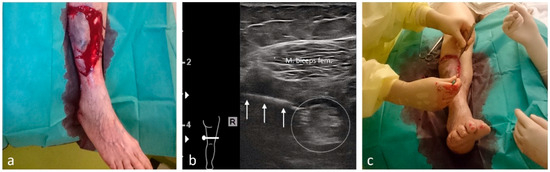

| Foreign body removal | 14 | Depending on location |

| Hematomas and hemarthroses | 15 | Depending on location |

| Soft-tissue infections (extremities) | 46 | Depending on location |

| Large lacerations/cuts | 12 | Depending on location |